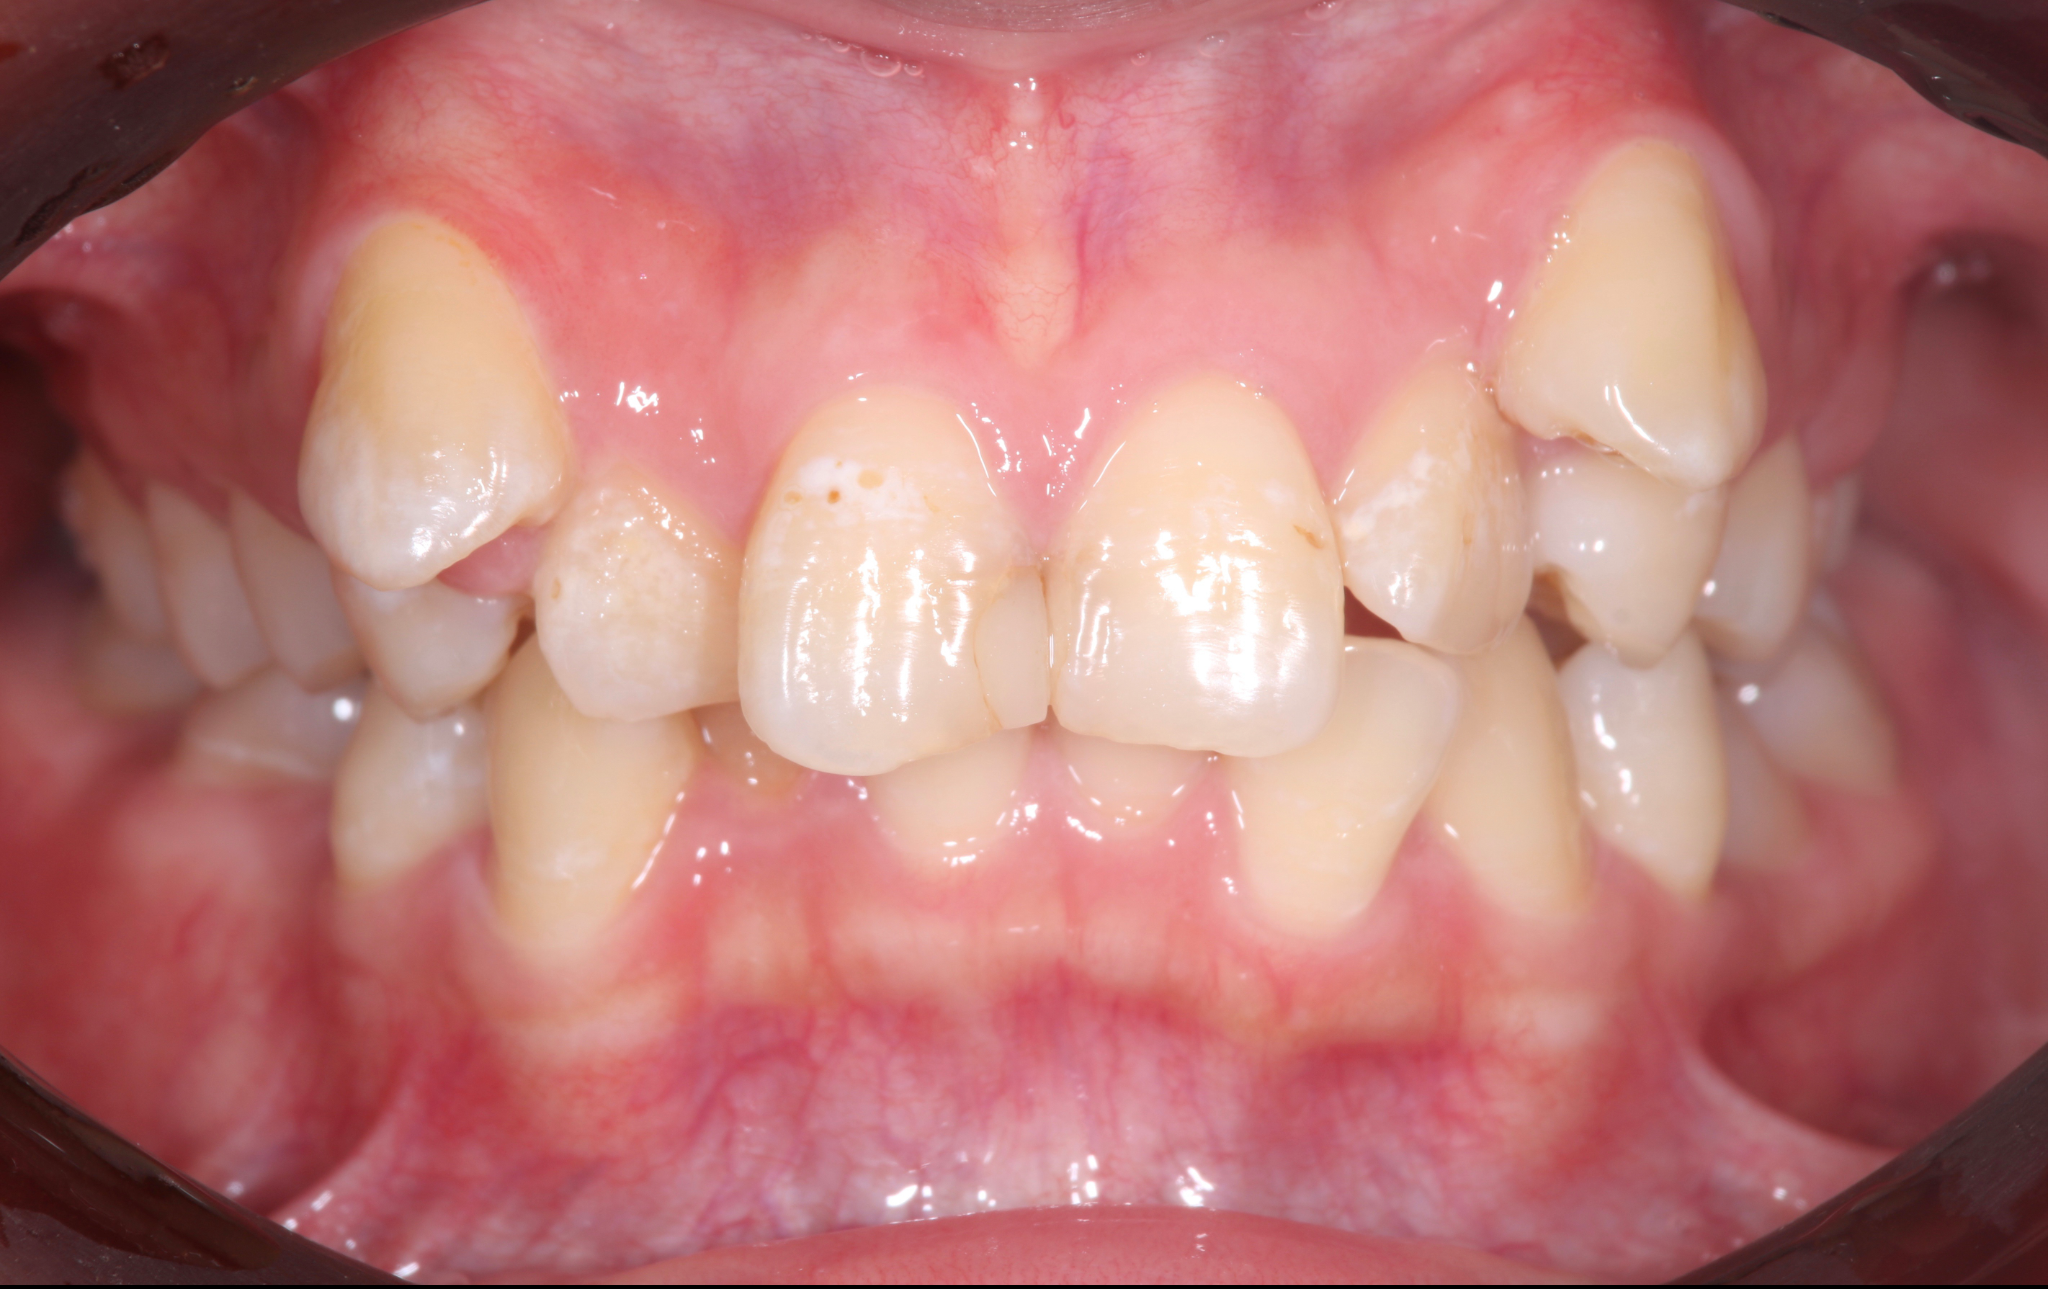

症例3:重度の叢生と開咬を矯正治療で改善した症例

術前の状態

術後の状態

治療概要

| 患者さんの状態 | 重度の叢生と開咬 |

|---|---|

| 治療内容 | MEAWを用いた矯正治療(非抜歯) |

| 治療期間 | 約2年 |

| 治療費用 | 1,320,000円(税込) ※矯正治療費のみです。 |

| 治療のリスク | 歯肉退縮、自由診療、後戻り、口腔内清掃が難しい |